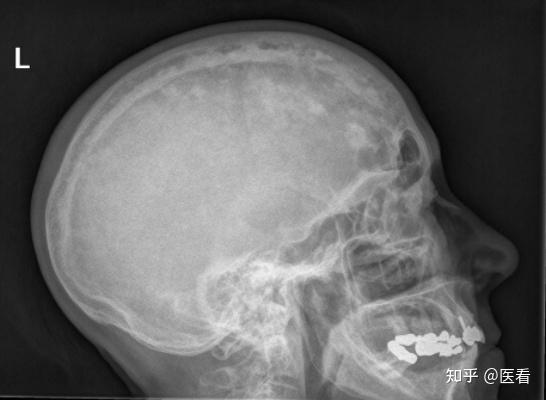

颅骨纤维结构不良,paget病丨影像诊断相关要点_医学界

颅骨纤维结构不良,paget病:影像诊断相关要点_医学界